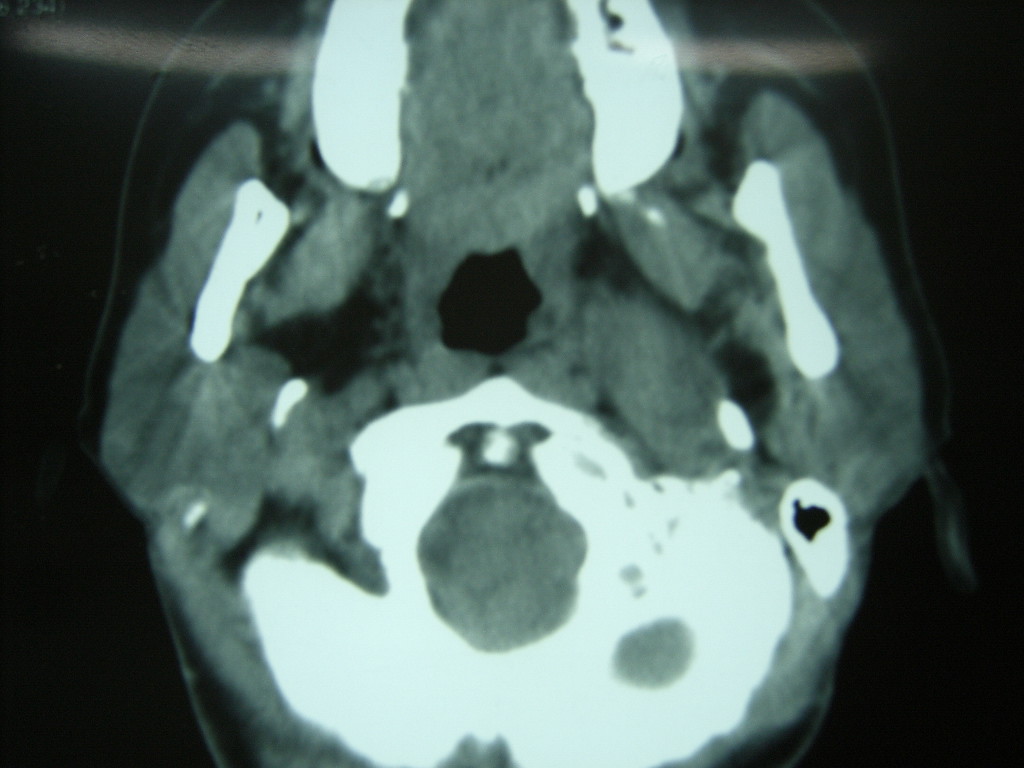

女,48岁,左颈部增粗,不适一年,伴左侧面麻.

增强明显,考虑左侧颈动脉体瘤可能性大。

颈动脉体瘤,不除外副节瘤。

左侧颈动脉体部肿瘤(以化学感受器肿瘤)可能性大。

答案:颈动脉体瘤  此患者已于赤峰220医院手术,